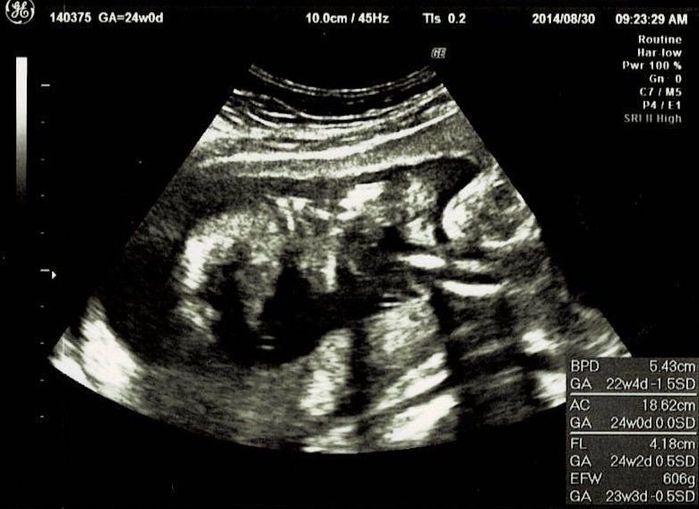

妊娠24週目エコー写真 お顔がなかなか見られない 夏の妊娠はとにかく暑い

夏真っ盛り。妊娠前の半袖ワンピースでどうにか乗り切っていましたが、腹帯なんて暑いものは耐えられず取ってしまいました。妊娠16周目と同じく、BPD、AC、FLを測ってもらいました。赤ちゃんのおおよその体重は606g。3Dエコーでお顔をきちんと見てみようとしますが、やはり手で隠してしまうため、なかなか見られませんでした。これでも顔が写っている一番いい3Dエコー写真です。